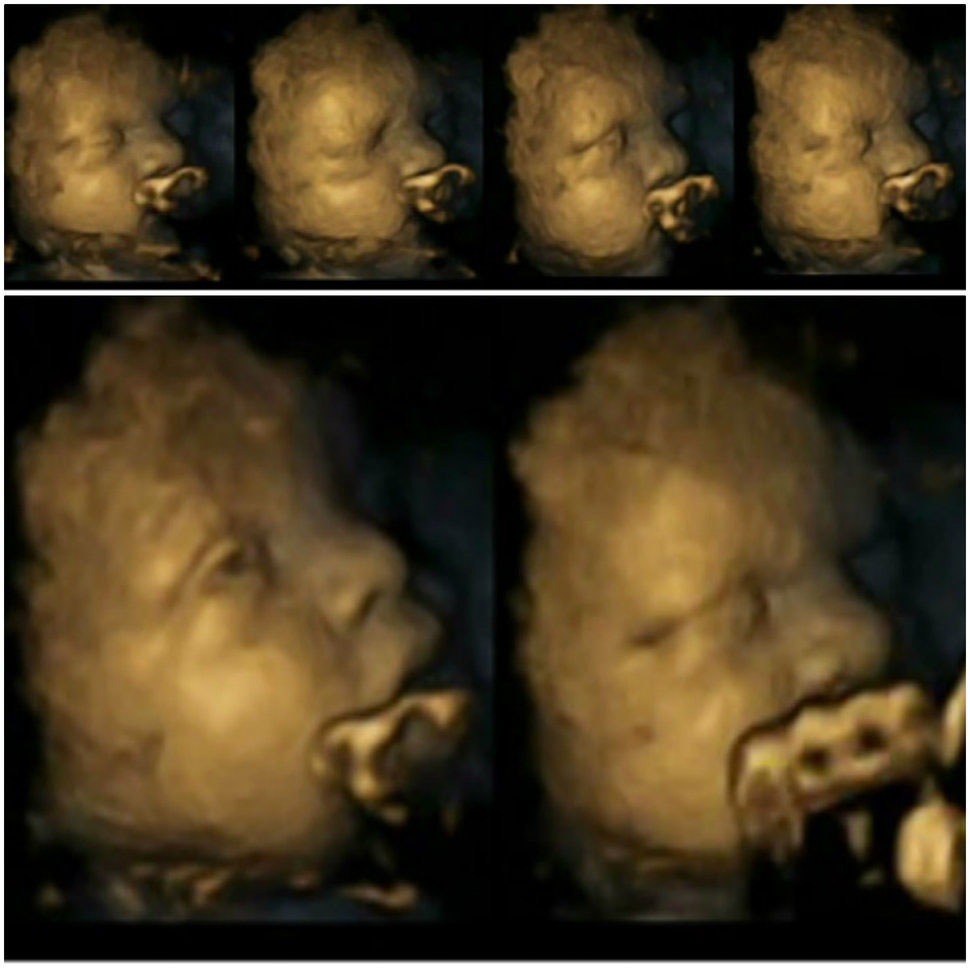

Aquí vemos un primer plano del feto expuesto al humo del cigarrillo. No somos científicos, pero nos parece seguro que está haciendo una mueca y frotándose los ojos. Algo así como lo que hacemos cuando alguien nos echa el humo de un cigarrillo en la cara.

Sin embargo, el feto de no fumadoras es así, como si durmiera una siesta. Como si no hubiera ninguna preocupación en el mundo.